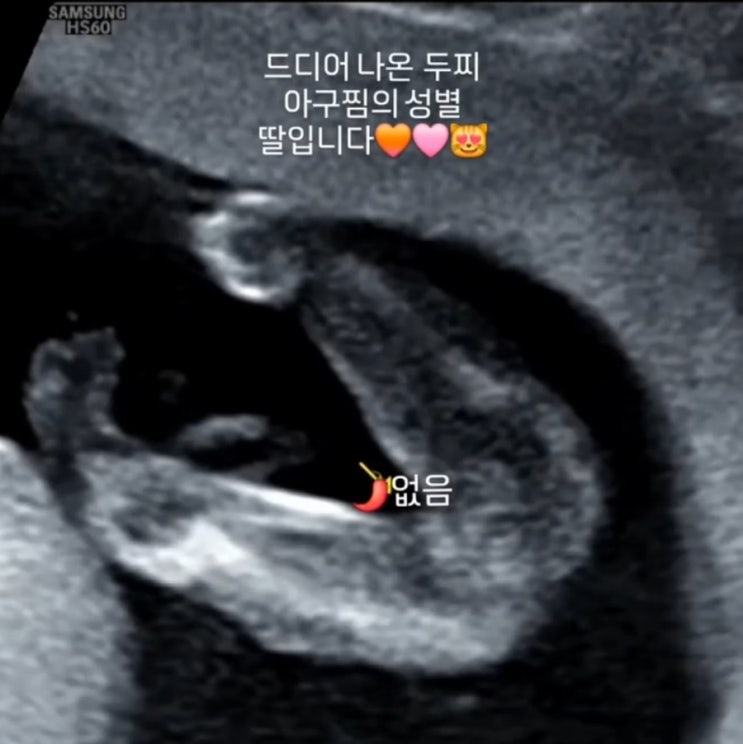

임신 16주, 성별 나왔다?

지금은 임신 20주인 나 우리 아구찜 언제크나 했는데 정말 쑥쑥 커주었다 배가 훅훅훅 나오면서 환도선다때...